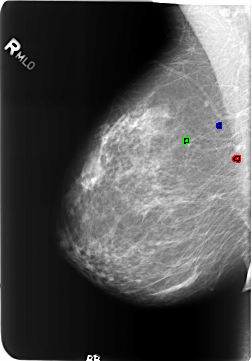

B_3223_1.RIGHT_MLO

FILE: B_3223_1.RIGHT_MLO.OVERLAY

TOTAL_ABNORMALITIES 3

ABNORMALITY 1

LESION_TYPE CALCIFICATION TYPE LUCENT_CENTER DISTRIBUTION N/A

ASSESSMENT 2

SUBTLETY 3

PATHOLOGY BENIGN_WITHOUT_CALLBACK

ABNORMALITY 2

ABNORMALITY 3